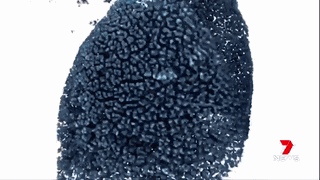

胰腺癌是最耐藥的病癥,已經(jīng)成為澳洲最致命的病癥。大多數(shù)被診斷為胰腺癌的病人會(huì)在半年內(nèi)死亡。

澳洲的科學(xué)家們通過運(yùn)用納米技術(shù),將“基因沉默”(gene silencing)藥物運(yùn)送至腫瘤細(xì)胞中來治療胰腺癌。

藥物已經(jīng)在擁有和人類相仿的瘢痕組織的小鼠身上進(jìn)行試驗(yàn),并獲得成功。